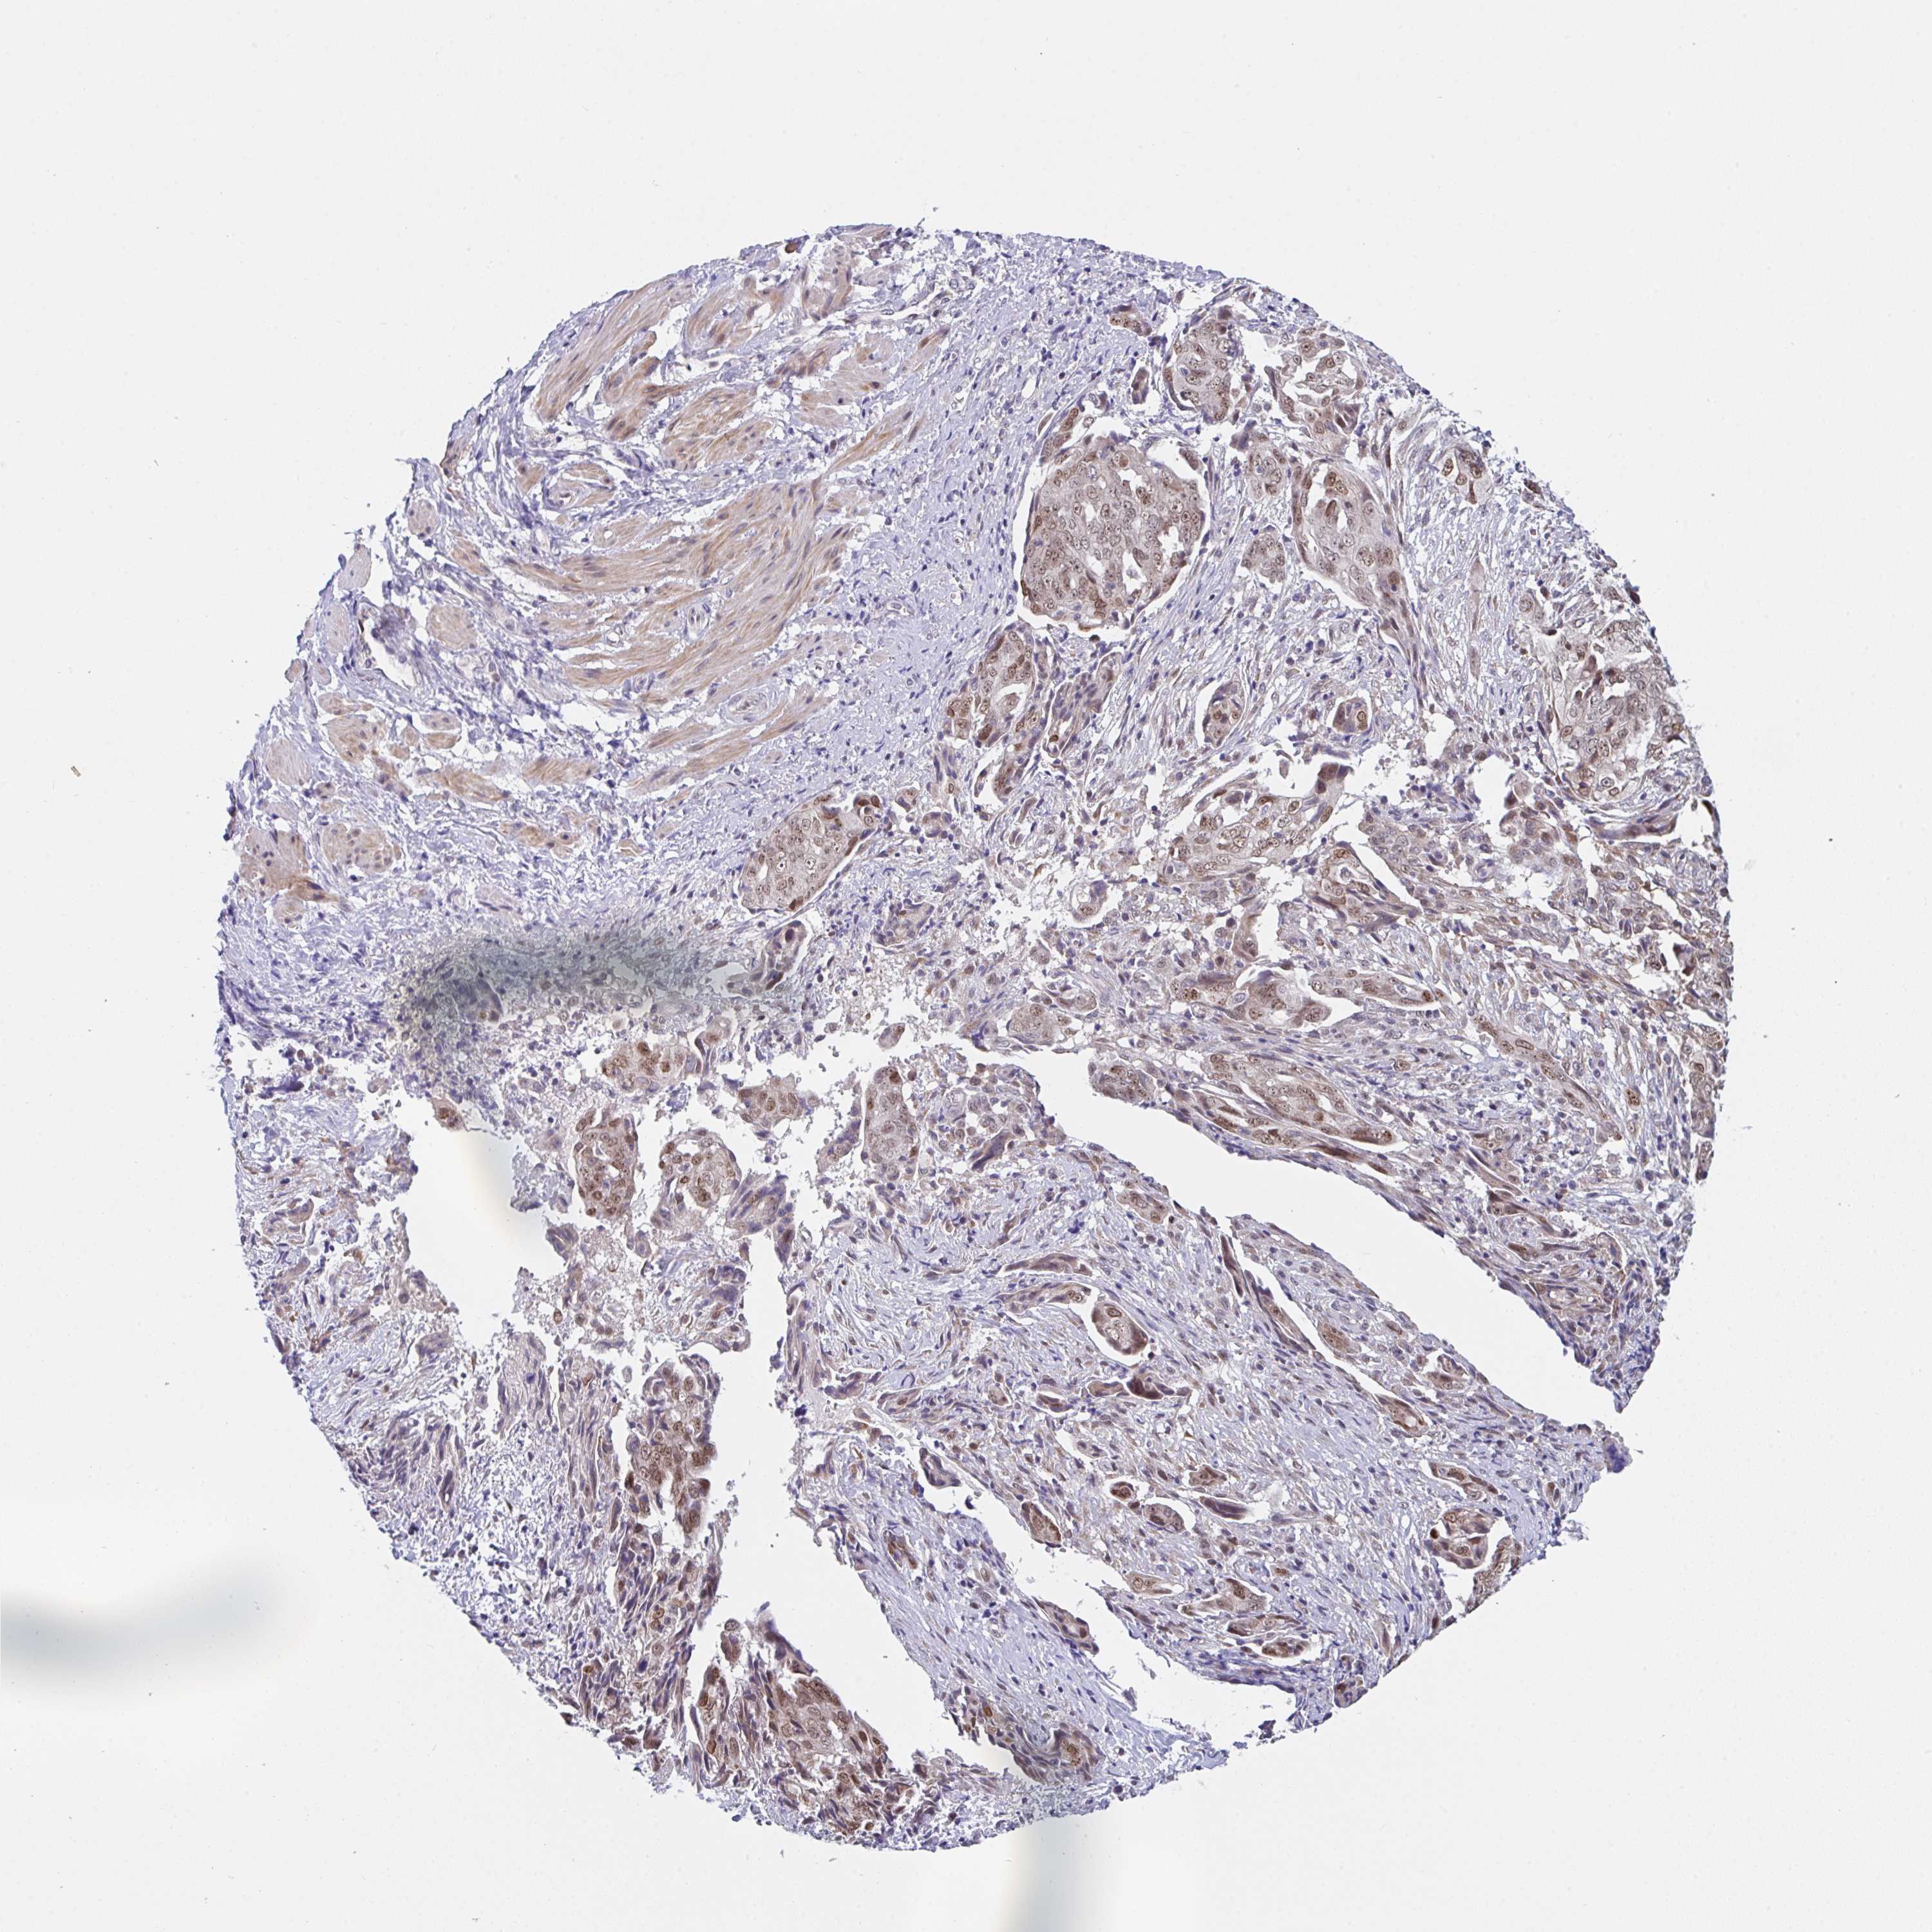

OVARIAN CANCER - Protein expressioni

A mouse-over function shows sample information and annotation data. Click on an image to view it in a full screen mode. Samples can be filtered based on level of antibody staining by selecting one or several of the following categories: high, medium, low and not detected. The assay and annotation is described here.

Note that samples used for immunohistochemistry by the Human Protein Atlas do not correspond to samples in the TCGA dataset.

Antibody stainingi

Antibody staining in the annotated cell types in the current human tissue is reported as not detected, low, medium, or high, based on conventional immunohistochemistry profiling in selected tissues. This score is based on the combination of the staining intensity and fraction of stained cells.

Each image is clickable and will lead to virtual microscopy that enables deeper exploration of all samples and also displays staining intensity scores, fraction scores and subcellular localization as well as patient and tissue information for each sample.

Antibody HPA057281

Staining

High

Medium

Low

Not detected

Intensity

Strong

Moderate

Weak

Negative

Quantity

>75%

75%-25%

<25%

None

Location

Nuclear

Cytoplasmic/membranous

Cytoplasmic/membranous,nuclear

Cystadenocarcinoma, serous, NOS

Cystadenocarcinoma, mucinous, NOS

Carcinoma, endometroid